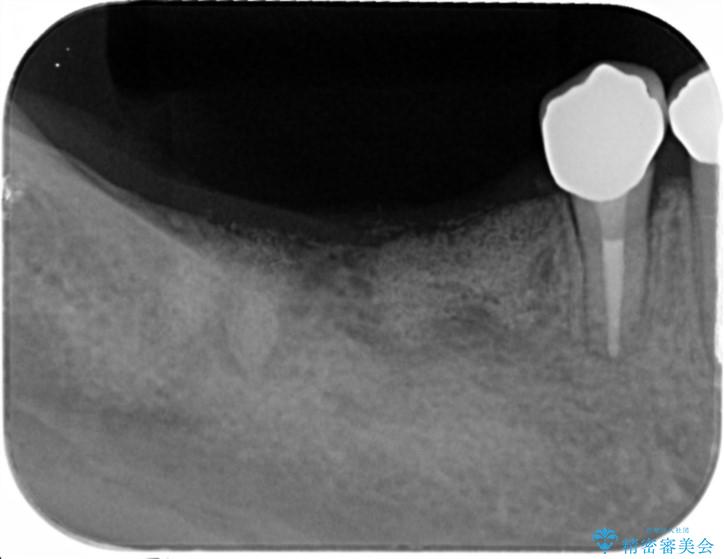

虫歯に伴い歯槽骨の吸収も見られたので造骨後、インプラントを用いて咬合機能を回復します。

また、機能後のインプラント周囲の清掃性を高めるため遊離歯肉移植術を行っています。

インプラント周囲に強固な歯ぐきを移植することで、歯ブラシがしやすくなりインプラント周囲炎対策となります。

治療中

遊離歯肉移植術を伴うインプラント治療 治療中画像 遊離歯肉移植術を伴うインプラント治療 治療中画像 遊離歯肉移植術を伴うインプラント治療 治療中画像 遊離歯肉移植術を伴うインプラント治療 治療中画像 遊離歯肉移植術を伴うインプラント治療 治療中画像 遊離歯肉移植術を伴うインプラント治療 治療中画像